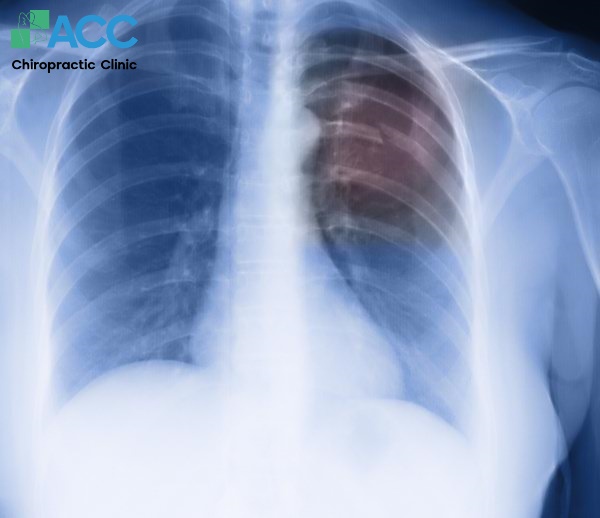

Bên cạnh các yếu tố kể trên, tình trạng bị đau sau lưng bên trái dưới bả vai hoặc bị đau sau lưng bên phải dưới bả vai có thể là triệu chứng cảnh báo các bệnh lý như thoát vị đĩa đệm cổ, trật xương sườn, gãy nén đốt sống hoặc các vấn đề về tim…

2.3 Gãy nén đốt sống

Gãy nén đốt sống là tình trạng các đốt sống tạo nên cột sống bị nén úp sụp xuống khiến vùng đốt sống đau dữ dội. Thông thường, bất cứ vị trí nào trên cột sống cũng có thể bị gãy nén nhưng phổ biến là xuất hiện ở vùng lưng dưới, dẫn đến tình trạng đau bả vai trái sau lưng hoặc phải sau lưng. Những người bị loãng xương, thiếu xương có nguy cơ bị gãy nén đốt sống cao hơn người thường.

2.4 Các vấn đề về tim

Bị đau sau lưng bên trái dưới bả vai khó thở hay bị đau sau lưng bên phải dưới bả vai khó thở – cũng có thể là biểu hiện cảnh báo các bệnh lý về tim. Ví dụ như phình động mạch chủ – xảy ra khi động mạch lớn nhất của tim bị rách, gây đau dữ dội không chỉ ở vùng ngực mà có thể lan ra lưng, vai và di chuyển xuống gần xương bả vai. Vì thế người bệnh không nên chủ quan nếu xuất hiện cơn đau bả vai phải sau lưng hoặc trái sau lưng kèm theo các dấu hiệu nghiêm trọng khác như khó thở, tức ngực, đổ mồ hôi lạnh hoặc chóng mặt,… hãy đi khám ngay để loại trừ nguy cơ bệnh tim và có hướng xử lý kịp thời.